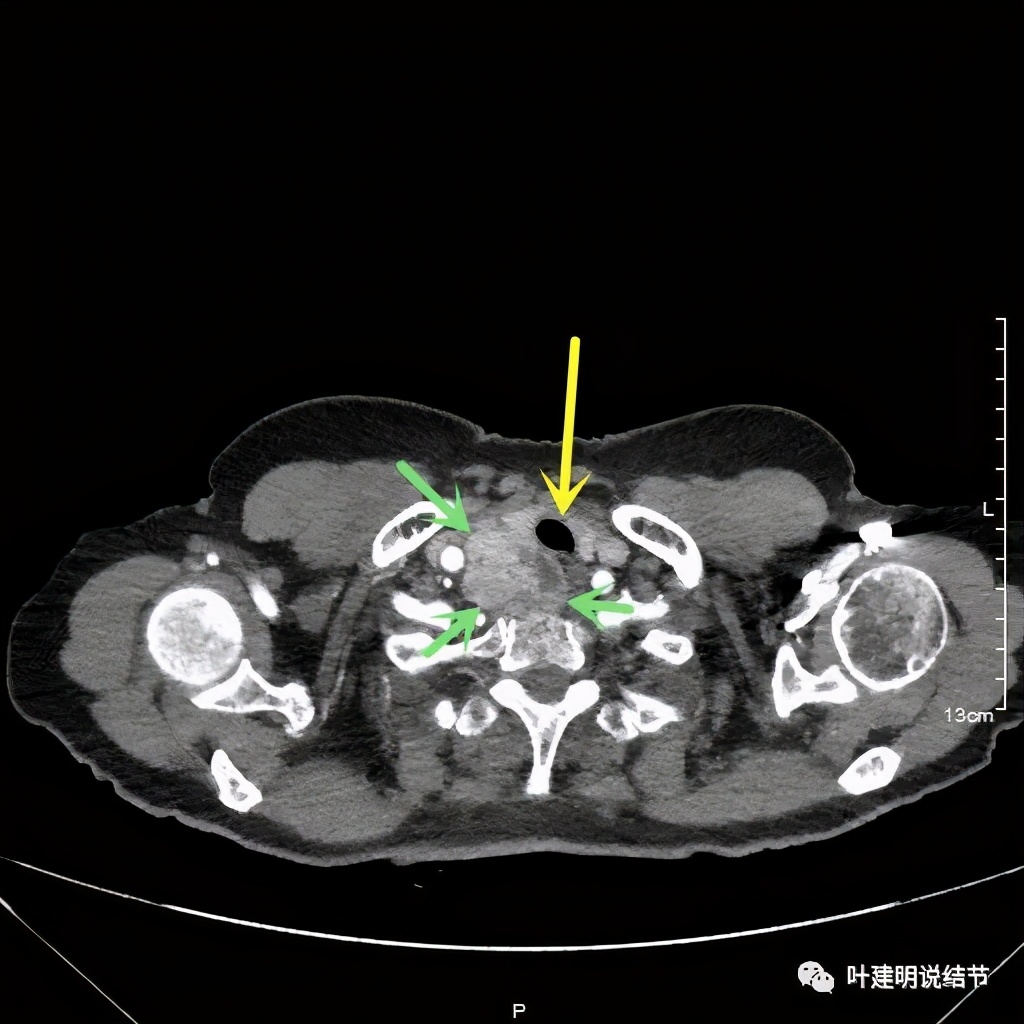

上图红色示肿瘤,黄色示气管,而且肿瘤密度不均杂乱

上图红色示肿瘤,粉色示肿瘤与气管关系密切,而且肿瘤密度不均杂乱

上图红色示肿瘤,黄色示气管,粉色示肿瘤与气管关系密切,而且肿瘤密度不均杂乱